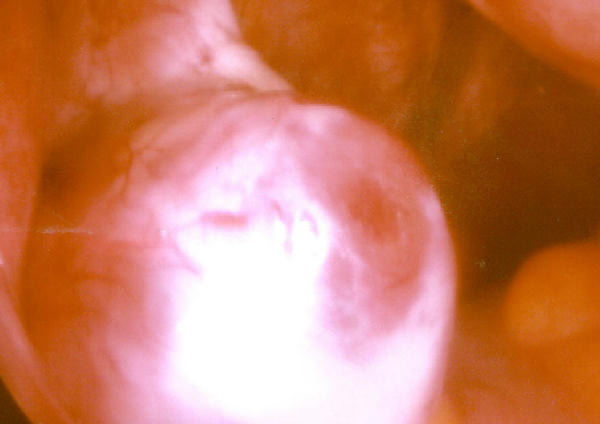

Source: Ovulation.jpg

Date: 7 April 2005

Author: ekem

Licence: Public domain